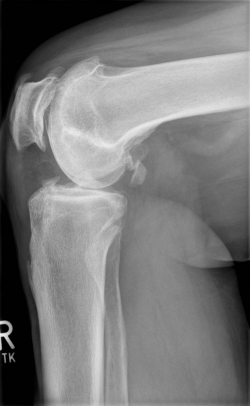

X-rays can be used to reliably diagnose the extent of joint wear. In the case of high-grade gonarthrosis, for example, the joint space and the formation of jagged edges (bone attachments, "osteophytes") as well as axial malalignment can be detected. If additional damage to the internal structures of the knee is suspected, ultrasound examination (sonography) or magnetic resonance imaging (MRI) can help clarify the situation.

Example X-ray images before and after implantation of a Persona knee prosthesis with robot.

Röntgenbild vor OP von vorn Röntgenbild vor OP von seitlich

a) präoperative Röntgenbilder des kranken Knies in 2 Ebenen